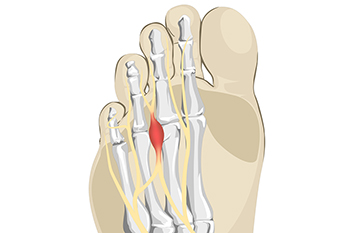

Leading Cause of Morton’s Neuroma

Morton’s neuroma is a condition that involves the feet. The medical name for this is known as Morton’s metatarsalgia or interdigital neuroma, and it affects the nerve between the third and fourth toes. Wearing high heels that do not have adequate room in the toe area is the leading cause of Morton’s neuroma. Wearing these types of shoes may cause this nerve to become compressed and is often painful and uncomfortable. Additionally, it may happen to patients who frequently participate in running and jumping activities, or to people who have flat feet or high arches. Common symptoms that are associated with this condition can include a tingling sensation that may eventually become a sharp and shooting pain. Numbness can accompany this ailment, and relief may be found when looser shoes are worn. If you have this type of pain, it is suggested that you contact a podiatrist who can provide treatment options, which may include wearing custom-made orthotics.

Morton’s Neuroma

Morton's neuroma is a painful foot condition that commonly affects the areas between the second and third or third and fourth toe, although other areas of the foot are also susceptible. Morton’s neuroma is caused by an inflamed nerve in the foot that is being squeezed and aggravated by surrounding bones.

Morton's Neuroma

A neuroma is a thickening of nerve tissue and can develop throughout the body. In the foot, the most common neuroma is a Morton’s neuroma; this typically forms between the third and fourth toes. The thickening of the nerve is typically caused by compression and irritation of the nerve; this thickening can in turn cause enlargement and, in some cases, nerve damage.

Neuromas can be caused by anything that causes compression or irritation of the nerve. A common cause is wearing shoes with tapered toe boxes or high heels that force the toes into the toe boxes. Physical activities that involve repeated pressure to the foot, such as running or basketball, can also create neuromas. Those with foot deformities, such as bunions, hammertoes, or flatfeet, are more likely to develop the condition.

Symptoms of Morton’s neuroma include tingling, burning, numbness, pain, and the feeling that either something is inside the ball of the foot or that something in one’s shoe or sock is bunched up. Symptoms typically begin gradually and can even go away temporarily by removing one’s shoes or massaging the foot. An increase in the intensity of symptoms correlates with the increasing growth of the neuroma.